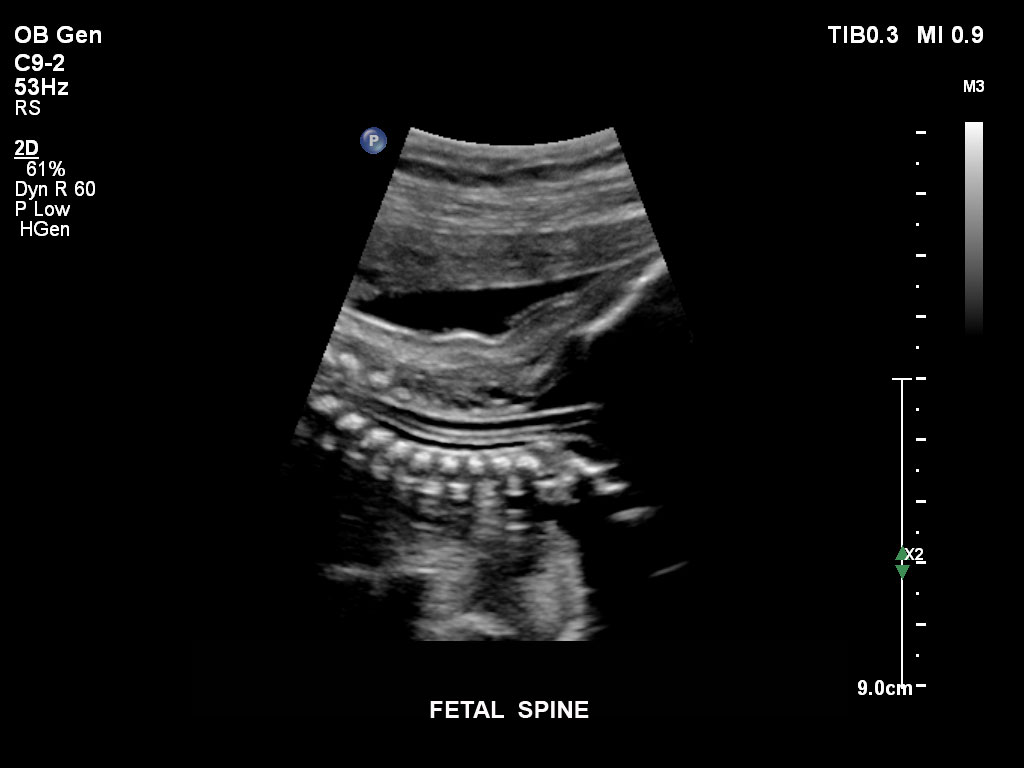

• C9-2 PureWave-Breitband-Convex-Schallkopf für Hochfrequenz-Bildgebung in der Gynäkologie und der Geburtshilfe, insbesondere für die Untersuchung im Hinblick auf mögliche Anomalien im ersten Schwangerschaftstrimester

• C5-1 PureWave-Breitband-Convex-Schallkopf für hohe Eindringtiefen in der Gynäkologie und der Geburtshilfe, für Patientinnen mit Schwangerschaftsdiabetes oder vorzeitigem Blasensprung